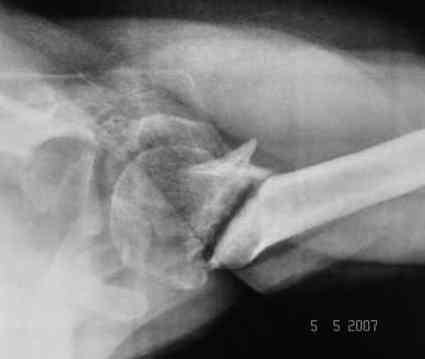

Looking at his previous x-rays, I was thinking of refixing the greater tuberosity, however got anaxillary view done today which was never done during this period and this shows non-union.

It looks like the initial injury was a head splitting fracture. Presently the patient has a non-union at the level of the anatomical neck with displaced tuberosities. I would tackle the non-union, and would try to replace the tuberosities, a difficult procedure. I would use the proximal humerus locking plate from the AO.

However, even if all goes well ( a big if!), the prognosis for regaining movement sufficient to tie his turban is poor.